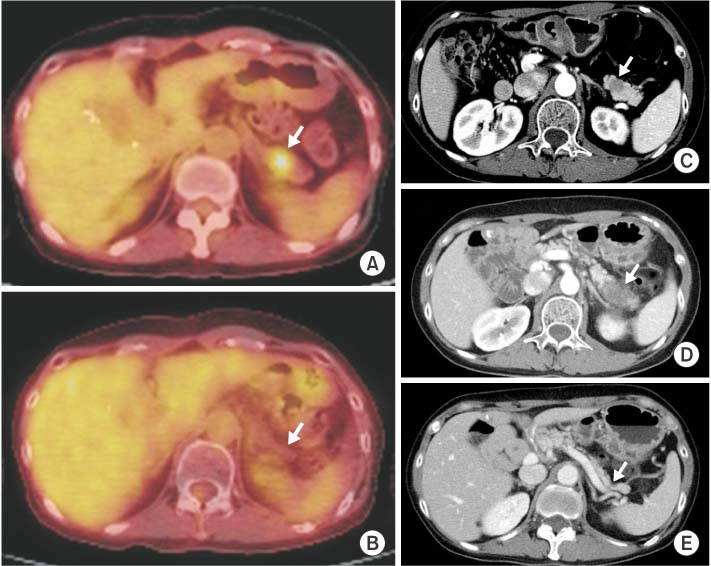

A 37-year-old woman was diagnosed with invasive ductal carcinoma of the right breast (Fig. 1). She underwent a total mastectomy and axillary lymph node dissection in May 2003. The tumor measuring 1.1 cm had no nodal or distant metastasis (pT1N0M0, stage I according to the 7th American Joint Committee on Cancer). Also it was an estrogen receptor-negative, progesterone receptor-negative and HER2-positive tumor with low Ki-67 index (5%), as determined by immunohistochemistry assay. She received six cycles of adjuvant chemotherapy (cyclophosphamide, methotrexate, and 5-fluorouracil). In January 2007, a solitary pulmonary nodule, which was 1.8 cm in diameter, was detected on chest computed tomography (CT) (Fig. 2A); it was confirmed to be a metastasis from the breast via percutaneous needle aspiration. There was no other distant metastasis except for a single mass in the right lung on 18F-fluorodeoxyglucose positron emission tomography-CT (18F-FDG PET-CT) (Fig. 2B). Lobectomy of the right lower lobe was performed via open thoracotomy (Fig. 2C, D). Six cycles of paclitaxel plus trastuzumab were then administered, followed by 35 cycles of trastuzumab until progression. In March 2009, the pancreatic lesion was detected on 18F-FDG PET-CT with standardized uptake value of 7.7 (Fig. 3A). The mass was observed as a low attenuating lesion (1.5 cm) in the pancreatic head on a CT scan of the abdomen and pelvis (Fig. 3B). A pylorus-preserving pancreaticoduodenectomy was performed, and metastatic infiltrating ductal carcinoma was confirmed (Fig. 3C, D). She received two cycles of combination chemotherapy with doxorubicin and cyclophosphamide. And newly appeared small lymph nodes at the mesentery were detected, considered disease progression. Therefore, eight cycles of gemcitabine and navelbine were administered from June to November 2009. However, in May 2010, a metastatic lesion of the pancreatic tail was newly detected on 18F-FDG PET-CT (Fig. 4A), and the nodules in the mesenteric lymph nodes became unremarkable. This pancreatic tail lesion was 1.5 cm in diameter on the CT scan (Fig. 4C). She received image-guided radiation therapy (IGRT) of 45 Gy in three fractions but the mass increased to 4 cm, as observed on a CT scan obtained the next month (Fig. 4D). Lapatinib plus capecitabine regimen was initiated in July 2010, and these treatments were continued over 4 years. The pancreatic tail lesion disappeared on an 18F-FDG PET-CT scan obtained in January 2011 (Fig. 4B) and on an abdominal-pelvic CT scan obtained in May 2011 (Fig. 4E). The pancreatic tail mass has been in complete response for 48 months since May 2011. A 25% dose reduction of lapatinib from the original dose was done in only one cycle due to grade 2 hyperbilirubinemia. The dose of capecitabine was reduced by 25% from the 3rd to 26th cycles due to grade 2 diarrhea and has been administered at 60% of the original dose from the 27th cycle until now.

Fig. 3

Radiologic and microscopic findings of pancreatic head lesion. (A) An 18F-fluorodeoxyglucose positron emission tomography computed tomography scan shows a hypermetabolic lesion (standardized uptake value, 7.7) in the pancreatic head. (B) This lesion is a low-attenuating mass (1.5 cm) on an abdominal-pelvic computed tomography scan. (C) Microscopically, the tumor cells show a small nest-like pattern with infiltrative features in the fibrous stroma (H&E, ×100). (D) Tumor cells are strongly immunoreactive for C-erbB2 (×200).

Fig. 4

Radiologic findings of pancreatic tail lesion with complete response. The pancreatic tail mass has been initially shown as a hypermetabolic lesion (standardized uptake value, 3.3) on an 18F-fluorodeoxyglucose positron emission tomography computed tomography (18F-FDG PET-CT) scan (A) and as a low-attenuating lesion (1.5 cm) on an abdominal-pelvic CT scan (C). After image-guided radiation therapy of 45 Gy, enlarged mass is shown (D). However, after combination chemotherapy with lapatinib and capecitabine, this pancreatic tail mass disappeared on 18F-FDG PET-CT (B) and CT (E) scans.